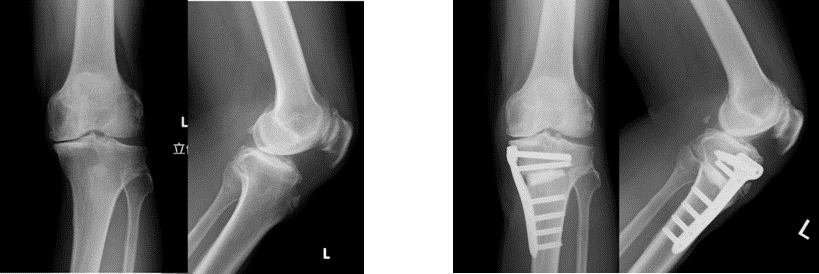

高位脛骨骨切り術 (high tibial osteotomy: HTO)

変形性膝関節症や大腿骨内顆骨壊死症などに適応があります。

脛骨の近位部を骨切りし、O脚に変形した下肢を軽度X脚に矯正し、荷重による負担を膝外側に移動することによって、膝内側の痛みを緩和する方法です。変形の程度によって開大式と閉鎖式骨切り術を使い分けております。

また、若年者で骨壊死を伴う症例には、骨軟骨片移植による関節内治療も併用し、良好な成績を得ています。

高度X脚